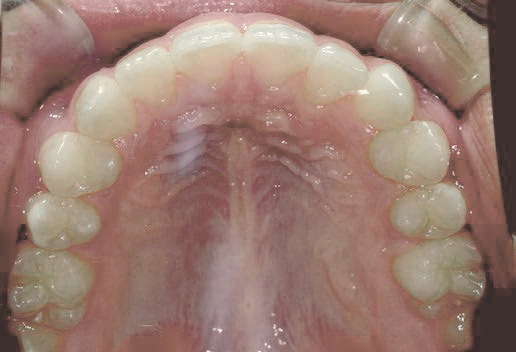

Mさん (矯正開始時:8歳)

Before

After

これから生えてくる永久歯のスペースがなく、歯が並ぶ余地がほとんどありませんでした。

さらに、上からあごの骨を見たところ、中央がくびれた“ひょうたん型”に変形しており、あごの成長にも偏りが見られました。

診断の結果、前歯の中心も少し左にずれており、特に犬歯が生えるスペースが足りない状態でした。

飲み込むときに下くちびるに力が入り、顔の左側にゆがみが出ている様子も確認できました。

治療を終えて

犬歯が歯ぐきの中に埋まっていたため、透明のマウスピース型装置で生えるスペースを作り正しい位置に導きました。もちろん抜歯せずに歯並びを整えることができました。お口の中がとても小さく、型どりの際にオエッとなる反応が強く、当時は装置を作るのが大変でした。しかし現在では3Dスキャナーと3Dプリンターを活用しスムーズに治療できます。

主訴・治療内容 「あごが小さいから、歯がきれいに並ばない」と他院で言われ永久歯を抜く矯正をすすめられていました。

本当に非抜歯で治療できるのか心配されていましたが、治療方法を丁寧にご説明し、お任せいただきました。

治療期間 5年

費用 550,000円(税込)